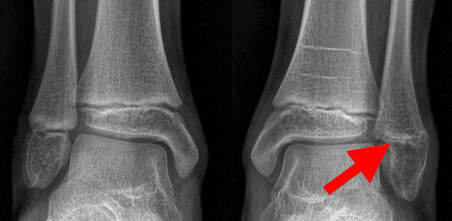

Medial Malleolus Fractures

The medial malleolus is the bony bump on the inside of the ankle. When a child twists their ankle, the medial malleolus can fracture. This results in a small, often unstable fragment. Because medial malleolus fractures tend to occur in younger patients, problems arising from a growth disturbance can be more severe. If the fragment is non-displaced or minimally displaced, it can be treated with a long-leg cast. Because this fracture fragment is small and usually unstable, it is usually treated with screw and/or pin fixation.

This X-ray shows a fractured and displaced medial malleolus. The bone fragment was reduced to its normal position and stabilized with a screw and two pins. Screw fixation alone is typically adequate.